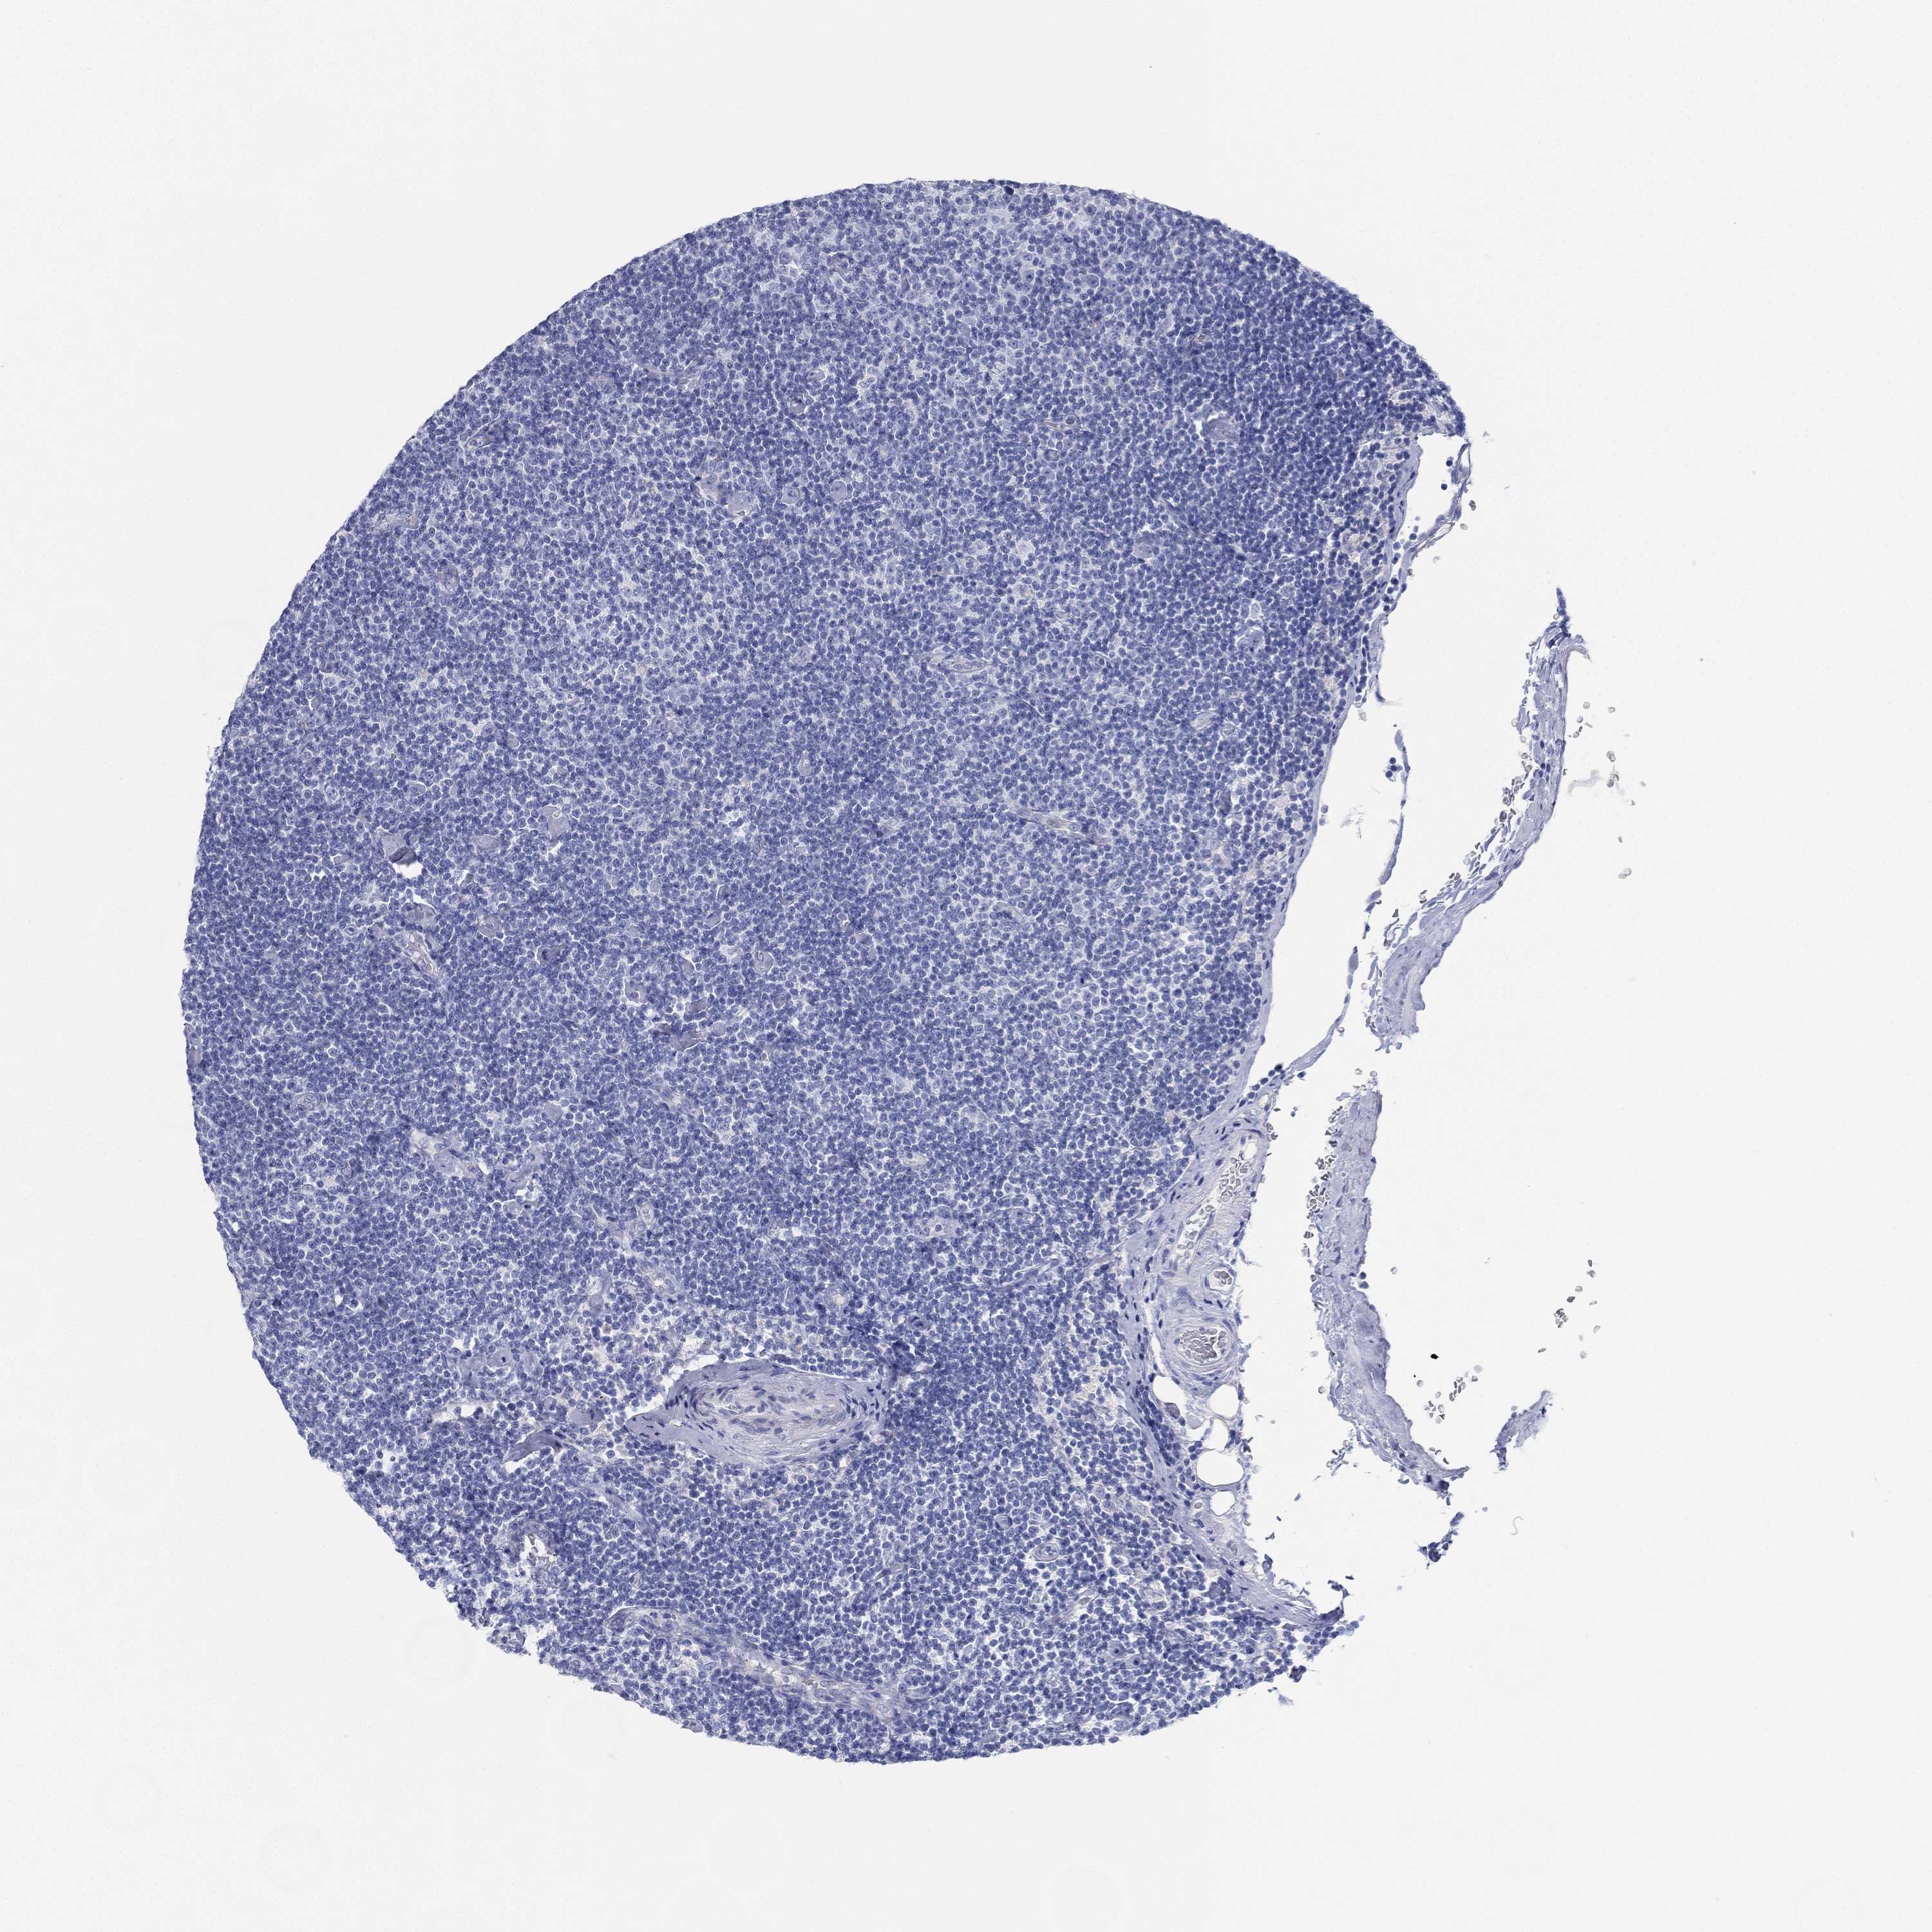

CANCER LYMPHOMA Show tissue menu

LYMPHOMA - Protein expressioni

A mouse-over function shows sample information and annotation data. Click on an image to view it in a full screen mode. Samples can be filtered based on level of antibody staining by selecting one or several of the following categories: high, medium, low and not detected. The assay and annotation is described here.

Each image is clickable and will lead to virtual microscopy that enables deeper exploration of all samples and also displays staining intensity scores, fraction scores and subcellular localization as well as patient and tissue information for each sample.

Antibody HPA007326

Malignant lymphoma, non-Hodgkin's type, Low grade

Malignant lymphoma, non-Hodgkin's type, High grade

Hodgkin's disease, NOS